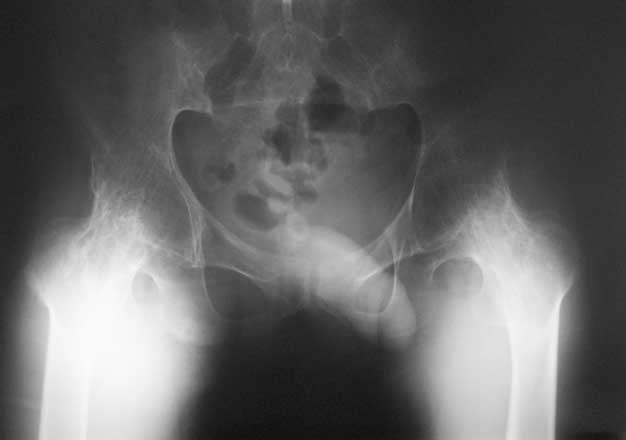

Уважаемые коллеги, в отделении находится пациент 28 лет, страдающий ревматоидным артритом с детства. В настоящее время основной проблемой для него являются тазобедренные суставы - костный анкилоз в положении сгибания около 80 град.

Привет Максим. На двух анкилозах передвигаться крайне плохо. Раз ходит - то небольшая часть мышц окружности т.б сустава есть, это видно и на фото. Пошел бы по пути разанкилозирования и бесцементник с каждой стороны поочередно.

Максим, мы протезировали 2х подобных больных. В случае с семилетним анкилозом на фоне болезни Бехтерева функция сустава осталась значительно ограниченой, но больная вполне сносно передвигалась. В другом случае на фоне ревматоидного артрита 4х летний анкизоз у молодого парня получен очень хороший функциональный результат. В обоих случаях использовали бесцементные протезы.

Следует учесть тот факт, что нечто принимаемое за хорошую кость во впадине по рентгенограмме, может оказаться очень неприятной пустотой с порозными балочками. При выборе размеров чашки это следует учесть, а в целом результаты не разочаровывают.

Я бы делал все в один этап, т.к. ситуация по контрактуре не критична. Но при любых анкилозах есть трудности - прежде всего - направление остеотомии шейки бедра. При использовании переднего доступа очень легко ошибиться и "снести" заднюю стенку ВВ, лучше несколько раз перепроверить направление. Обязательно нужно сделать двойную остеотомию для создания необходимого про-ва для обработки ВВ. Необходимо очень не спеша определиться с маркерами ВВ, т.к. обрабатывать впадину Вы будете прямо по головке и иногда бывает сложно понять где находишься. В случае затруднения лучше сделать Р-контроль. В любом случае Вам надо сделать расширенный релиз для достижения хорошей интраоперационной амплитуды движений. И последнее - многие пациенты остаются неудовлетворенными р-ми операции из-за чувства нестабильности, "провала" в суставе, выраженной хромоты. Это связано с длительным бездействием мышц. Это не значит, что не надо делать операции, просто это надо иметь ввиду и объяснять пациентам.